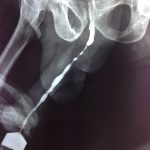

X-ray showing obstructing kidney with large kidney stone